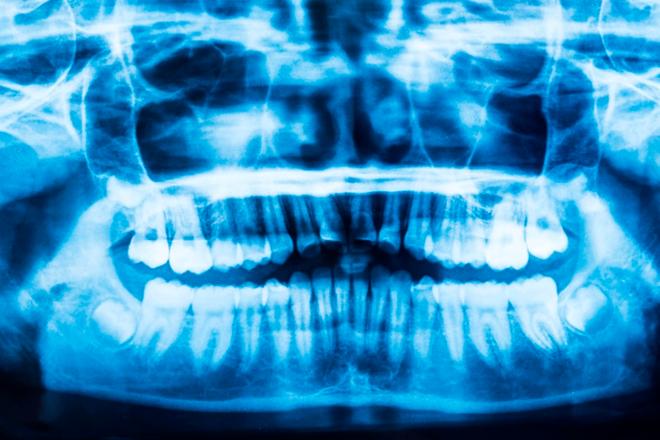

La protrusión dental es consecuencia de una maloclusión tipo II. Descubre cómo una ortodoncia puede corregir los dientes salidos o de conejo.

En el 80% de los casos el retrognatismo es de origen familiar, y se trata con una combinación de ortodoncia y cirugía.

¿Qué tipos de brackets se utilizan en los tratamientos de ortodoncia? Descubre los distintos tipos de brackets que existen.